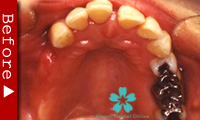

歯が全くない場合

下顎の歯が1本もない場合の修復には、インプラントが良く利用されます。

インプラントのヘッド部をバー状の維持装置で連結し、その上に取り外し式の入れ歯をしっかりと固定することができます。